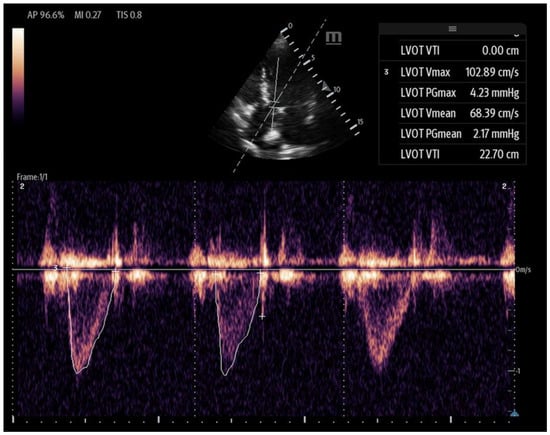

The VTI is measured in the apical five-chamber view using pulse-wave Doppler, with the sample volume placed at the center of the LVOT to trace the velocity curve (Figure 13). The VTI, measured in centimeters and averaged over several beats to account for beat-to-beat variability, reflects the distance that blood is propelled forward from the LVOT to the aorta with each contraction. When used in conjunction with blood pressure and lactate levels, the LVOT-VTI can help guide shock etiology as well. A low VTI with hypotension and elevated lactate suggests low-output shock (e.g., cardiogenic), and a high VTI with hypotension and elevated lactate may suggest distributive shock (e.g., early sepsis). The normal range is between 17 and 23 cm, and it serves as a surrogate for stroke volume. When used in conjunction with the clinical picture, the VTI can also serve as a valuable tool for longitudinal assessment and is shown to decrease total time on vasoactive agents [61].

Figure 13.

Left ventricular VTI calculated with PW Doppler with Doppler gate at LVOT.